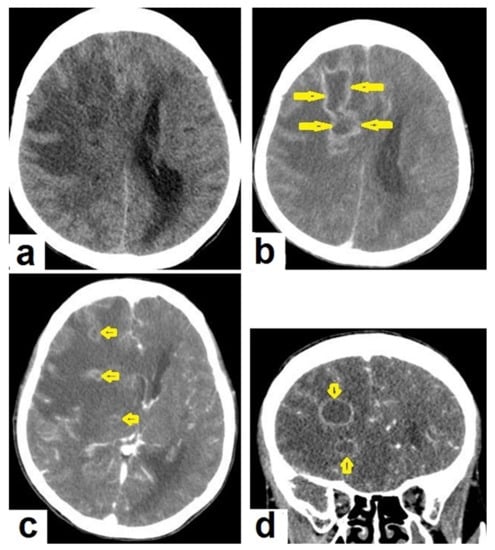

• Tuberculous abscesses (Figure 15, Figure 16 and Figure 17) are an infrequent pattern of brain TB, which are present in immunocompromised and elderly patients. They occur either due to the progression of cerebritis or the liquefaction of tuberculoma. On a brain CT, it occurs as a low density area with ring enhancement after contrast administration and the surrounding low density area of edema. On a brain MRI, it appears as a circular or elliptical area of low intensity with ring enhancement after contrast administration and surrounding low intensity area of edema on T1WIs and high intensity area with a high intensity surrounding edema. Tuberculous abscess is a difficult differential diagnosis of a pyogenic abscess, pilocystic astrocytoma, and other cystic lesions. MR spectroscopy may help in differentiating tuberculous from a pyogenic abscess [27,33].

Figure 15. Tuberculous abscesses and tuberculomas in a 70-year-old woman with disturbance of consciousness and long history of headache. Selected axial computed tomography (CT) images of the brain (a) axial non-enhanced CT show significant vasogenic edema in the frontal and parietal lobes of the right cerebral hemisphere, with severe mass effect manifested as loss of the cortical sulci, total effacement of the right lateral ventricle and mild midline shift to the left side. (b) Contrast-enhanced CT (CECT) shows loculated rim-enhancing lesion centered in the right frontal lobe measures about 39 mm × 16 mm × 12 mm, suggesting cerebral abscess (arrows). (c) Axial CECT shows multiple ring-enhancing lesions in the right cerebral hemispheres and right basal ganglia (short arrows) suggesting of cerebral abscesses or tuberculomas. (d) Coronal CECT shows multiple ring-enhancing lesions in the right cerebral hemispheres (short arrows), suggesting cerebral tuberculomas or abscesses.